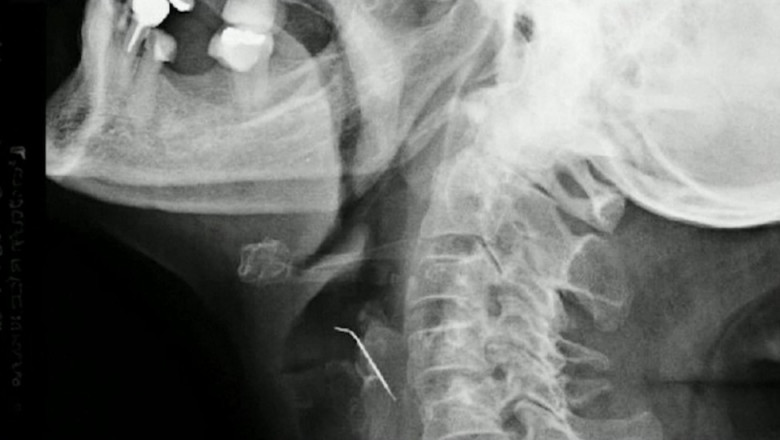

O femeie din Peru, în vârstă de 68 de ani, a ajuns de urgență la spital după ce a înghitit un obiect în timp ce mânca jumări de porc. După 43 de zile, femeia a fost operată de urgență, iar medicii au descoperit un cui lung de 5 centimetri în gâtul acesteia. O femeie în vârstă de 68 de ani din Peru a fost transportată de urgență la spital după ce a fost înghițit un cui în timp ce mânca jumări de porc. Starea gravă a femeii a fost neglijată timp de 43 de zile până când a căutat ajutor medical. Femeia a fost operată imediat, iar medicii au făcut o descoperire șocantă - un cui lung de 5 centimetri în gâtul acesteia, care se afla într-una dintre arterele carotide. Această situație extrem de rară și periculoasă a necesitat o intervenție chirurgicală complexă pentru a salva viața pacientei. "Ea a fost norocoasă că a ajuns la spital la timp, înainte de a suferi un accident vascular cerebral. Cuiul i-a străpuns artera și putea avea consecințe fatale", a declarat unul dintre medicii implicați în operație. Deși cazul femeii este unul rar, medicii avertizează că aceste situații pot apărea oricând și este important să se acționeze imediat pentru a evita complicații grave. "Este important să fim atenți la ceea ce mâncăm și să nu lăsăm la îndemâna copiilor obiecte care pot fi înghițite accidental", a atras atenția unul dintre specialiști. Intervenția chirurgicală de succes a fost prima de acest tip efectuată în Peru și unul dintre puținele cazuri înregistrate la nivel mondial. Femeia se recuperează acum la spital și este supravegheată de medici pentru a se asigura că nu apar complicații după operație.